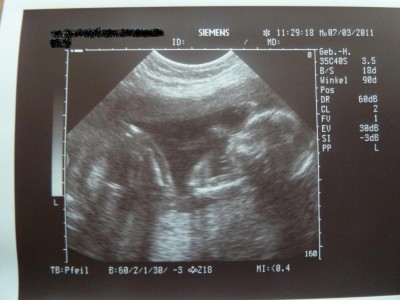

@all: war heute in der Kiwu zum Ultraschall. Ursprünglich wollte ich den Termin absagen, aber nach dem Gruseltermin letzten Montag habe ich mir das ganz schnell anders überlegt…So konnte ich heute endlich mal wieder ausführlich mein Babylein ansehen und danach ging es mir auch gleich vieeeeel besser. Habe heute auch endlich mal wieder ein paar Bildchen bekommen. Die stelle ich euch gleich mit ein. Der Kinderwagen wurde heute geliefert und so habe ich gleich mal fleissig alles geknipst. Bilder folgen. Seid alle lieb gegrüßt!!!